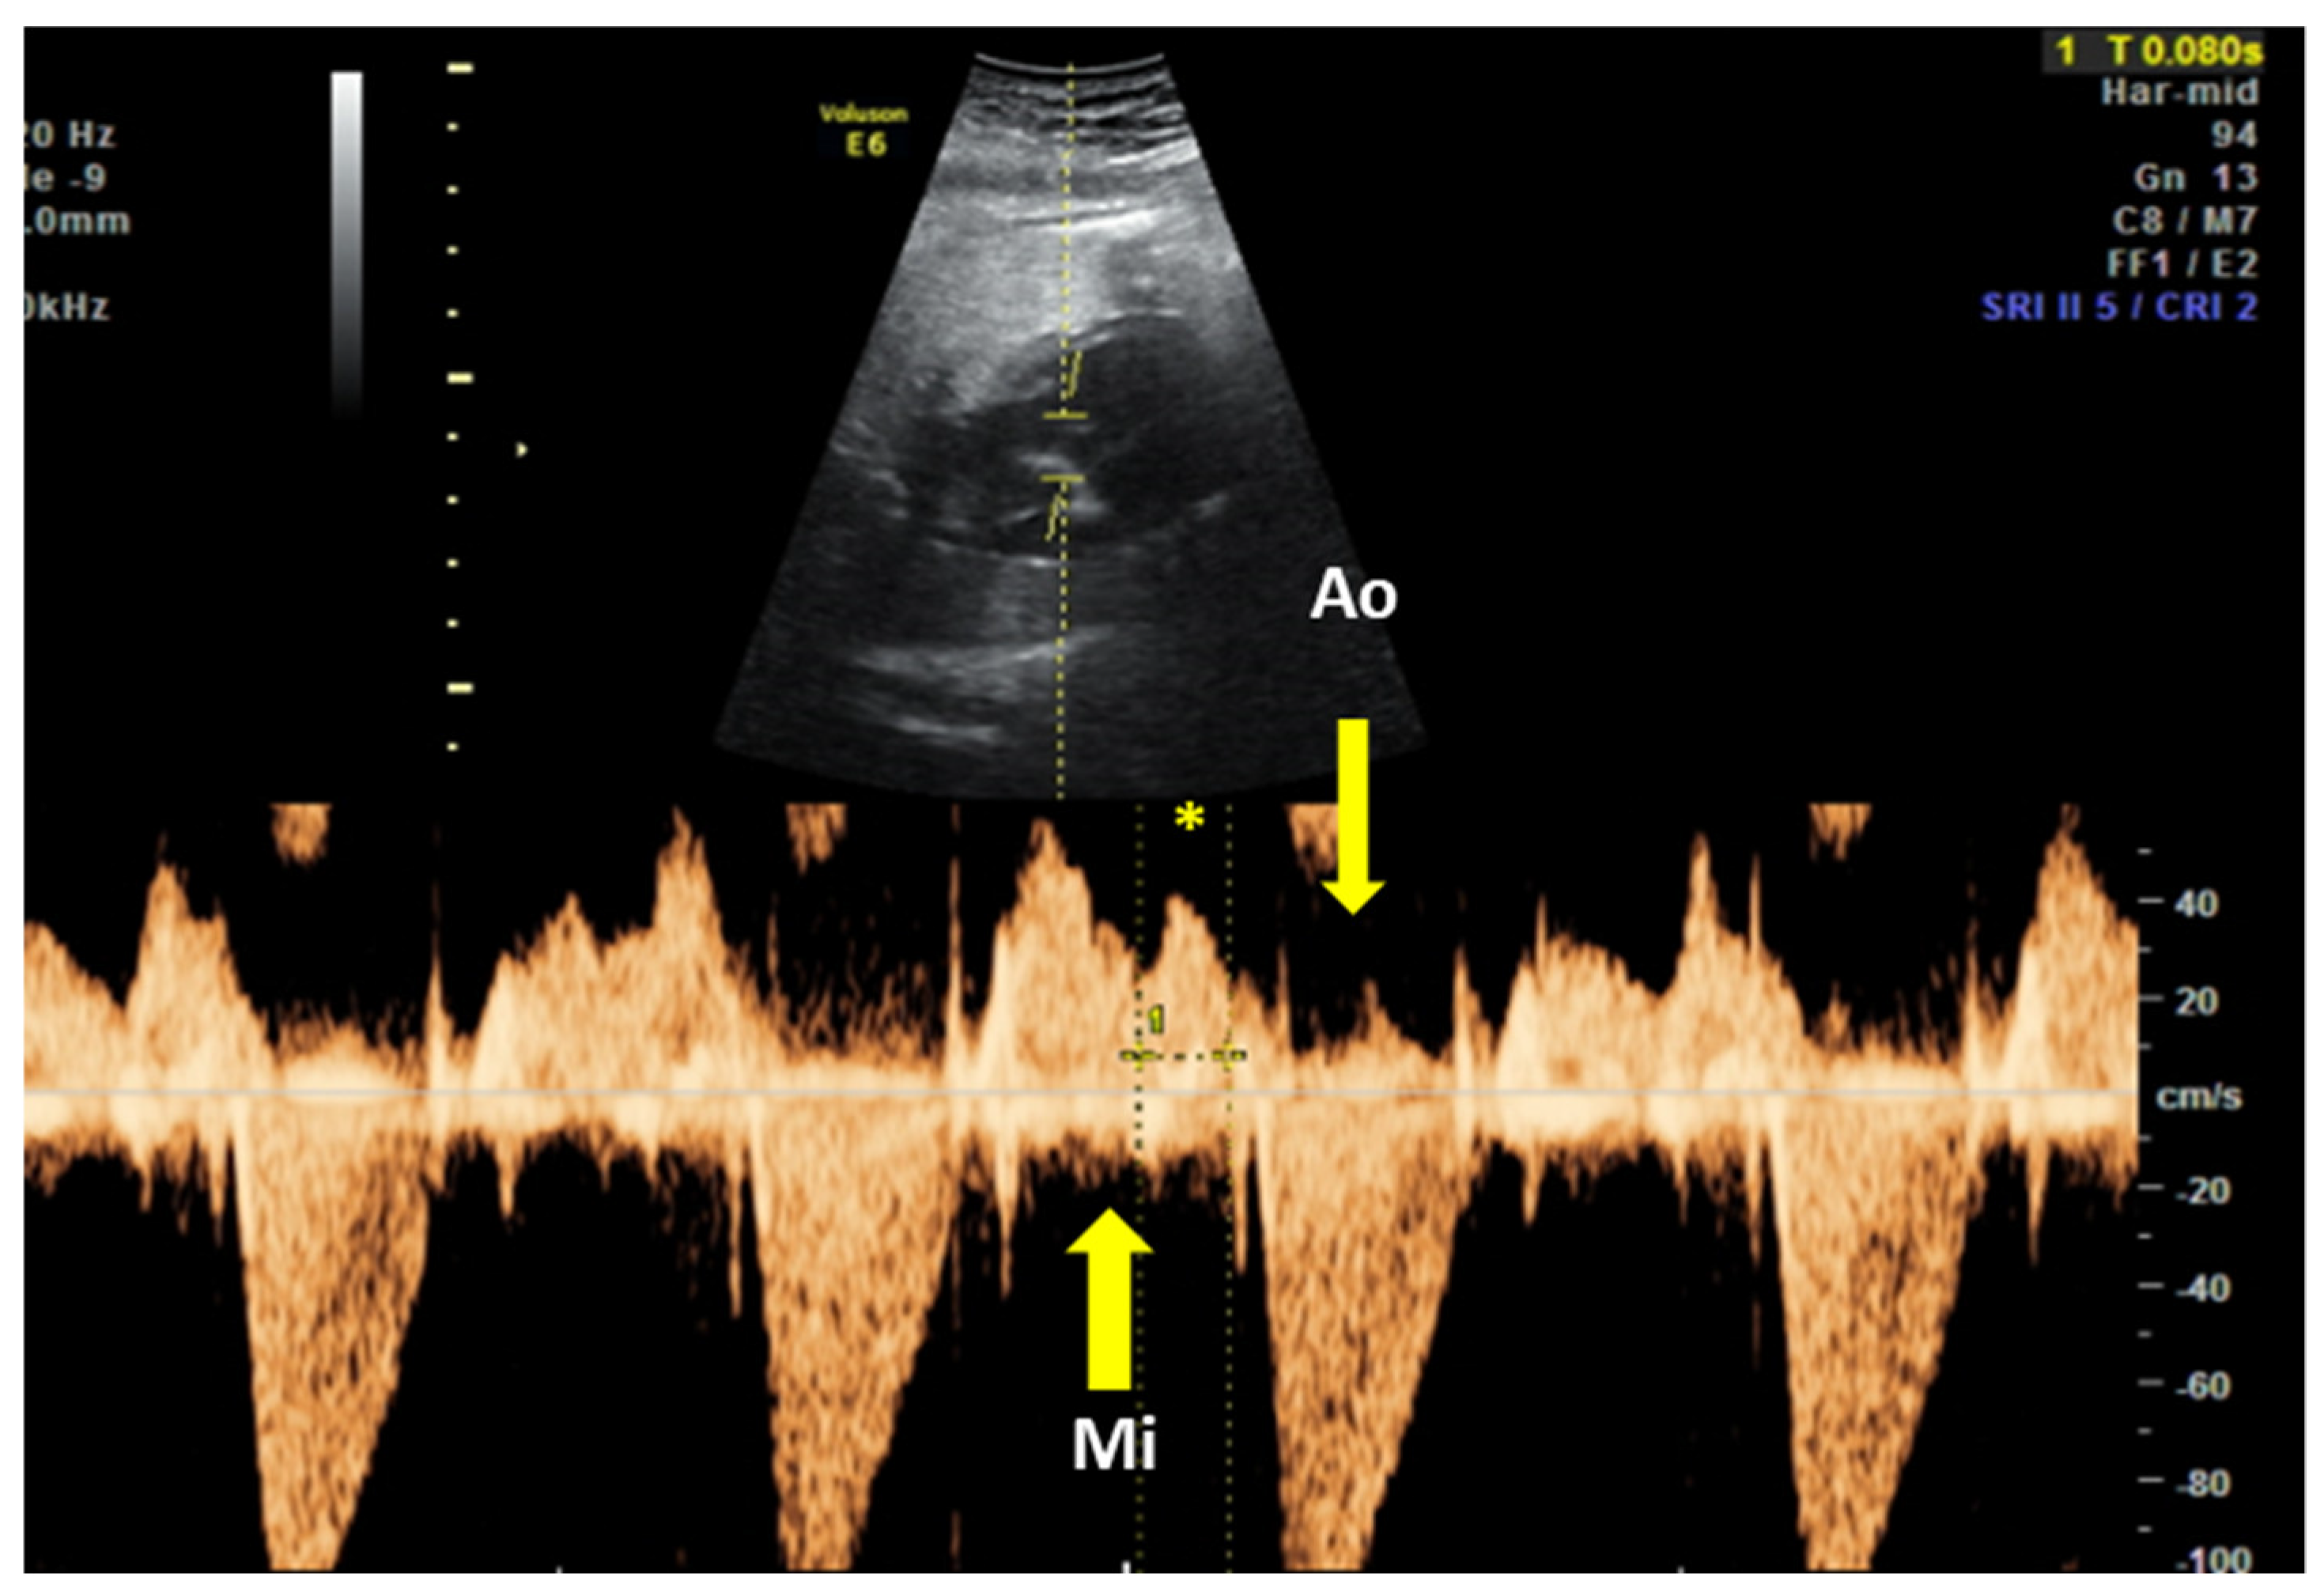

The fetal mechanical PR interval can be obtained during ultrasound examination of the fetal heart. It is recorded with the help of pulsed wave (PW) Doppler– the two-dimensional PW gate is set to 3–4 mm depending on the gestational age and placed distal to the mitral valve as such to include the origin of the left ventricle outflow tract at an angle of around 20°. With this approach, we will record spectral Doppler wave forms for both blood flows, in the mitral valve and aortic origin during a full cardiac cycle. The speed of image acquisition should be slowed (to 4–5 cm/s) in order to have a good representation of each waveform. During a normal cardiac cycle, the passive filling of the atria during generalized diastole (E wave), the active filling of ventricles during atrial systole (A wave) and blood ejection in the root of the aorta during ventricular systole will be documented (see Figure 4). The PR interval is the interval measured between the onset of atrial systole (mitral valve A-wave) and the beginning of the aortic valve flow. Normal ranges during pregnancy depend on the gestational age, fetal heart rate and sex of the baby. These correlations have been studied prospectively by A. Wojakowski et al. [78]. A mean of 122.4 ms ± SD 10.3 ms is considered normal.

Figure 4.

Pulsed wave Doppler trace used for mechanical PR interval measurement. Mi—transmitral flow (thick yellow arrow); Ao—transaortic flow (thin yellow arrow); (*)—normal PR interval—120 msec (between thin dotted yellow lines). Courtesy of Anca Panaitescu, Filantropia Clinical Hospital, Bucharest.

In a prospective trial of dexamethasone to prevent CHB progression in women with anti-Ro by Friedman et al. the definition of “abnormal” fetal Doppler mechanical PR interval was set a priori at three SD above the normal mean, to 150 ms [79]. However, none of the conduction measurements could predict the occurrence of CHB.